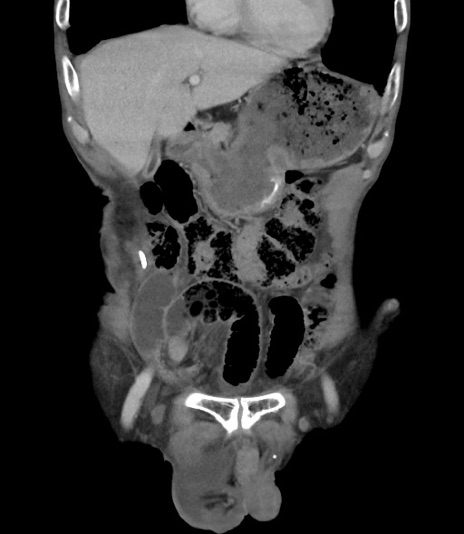

症例3(冠状断像)

【症例】 70歳代男性

【主訴】右鼠径部腫瘤、疼痛

【現病歴】本日朝より上記主訴あり、受診。

【既往歴】膀胱癌にて膀胱全摘、両側尿管皮膚瘻

【データ】WBC 5600、CRP 0.56